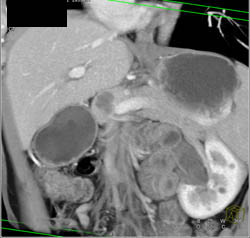

Splenic Tissue- in Tail of Pancreas